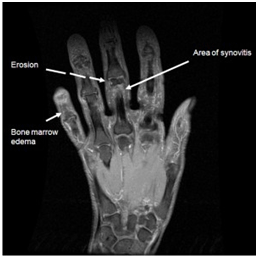

ΠΑΘΟΛΟΓΙΑ/ΠΑΘΟΓΕΝΕΣΗ

Η MRI υψηλής ευκρίνειας αναδεικνύει συχνά τις διαβρώσεις (Grainger et al, 2007). Οι οριακές διαβρώσεις συνδέονται με την παρουσία οιδήματος του μυελού των οστών και υπερτροφία του αρθρικού υμένα.

ΕΙΚΟΝΑ 1d. Μαγνητική τομογραφια σε ασθενή με ΔΟΑ : διαβρώσεις (διακοπτόμενο βέλος), υμενίτιδα (μακρύ βέλος) και οίδημα του μυελού των οστών (κοντό βέλος)